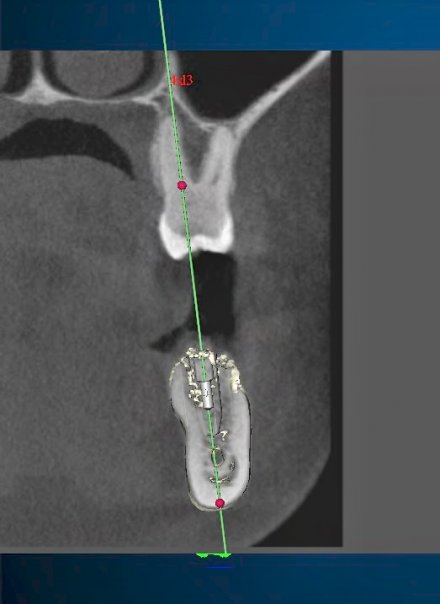

Computer Guided Implant Planning

CT Planning For Upper Jaw Implant